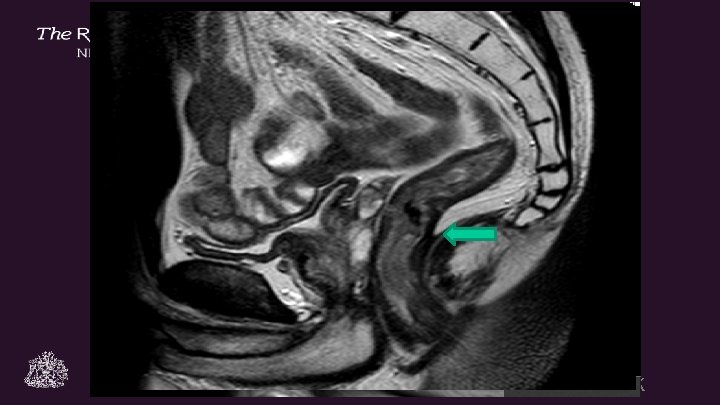

Discontinuous EMVI in ERC And a pelvic sidewall tumour deposit